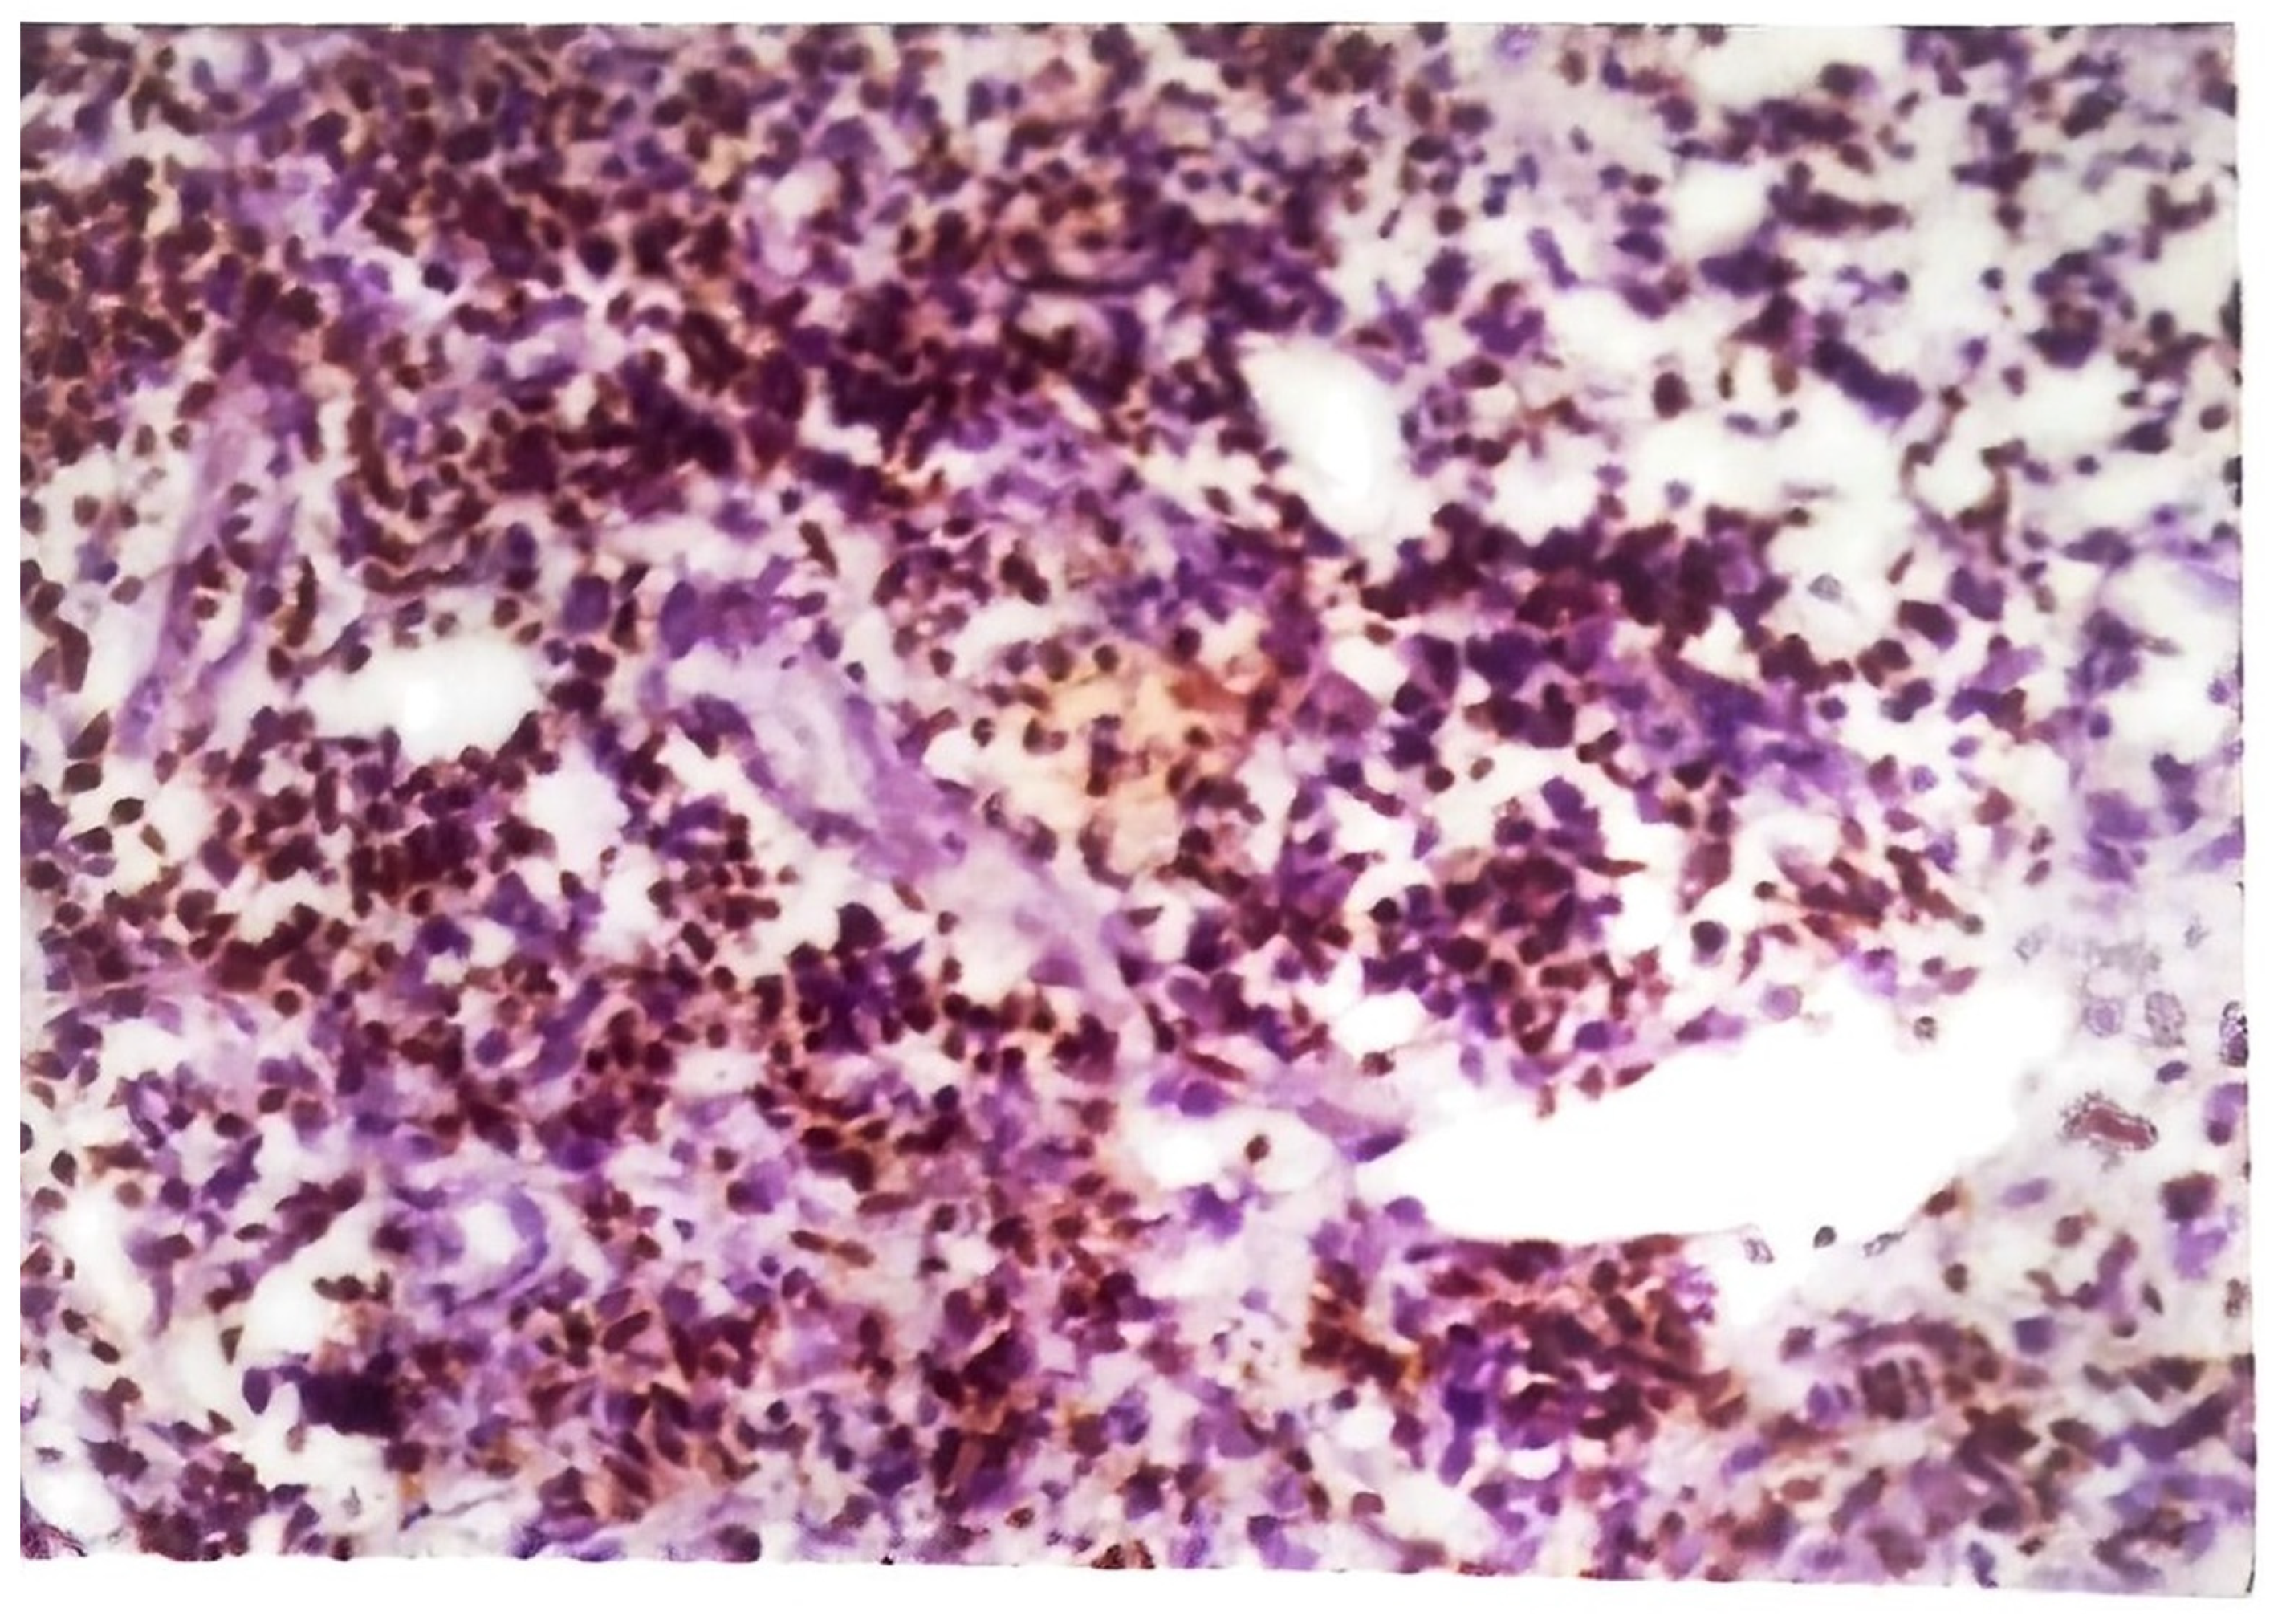

The histology of tuberculous chancres resembles that of an acute inflammatory reaction with areas of necrosis, numerous tubercle bacilli, and neutrophils [44]. After three to six weeks, the lesion involves granulomatous inflammation with increased numbers of giant cells and epithelioid cells and decreased number of identifiable tubercle bacilli. Healing may occur slowly with fibrosis and calcification [45]. Skin biopsy of tuberculous verrucosa cutis (Figure 6) shows hyperkeratosis, papillomatosis, and pseudoepitheliomatous hyperplasia of the epidermis as well as tuberculoid granulomas in the dermis. In about a third of patients with verrucosa cutis lesions, neutrophilic microabscesses were present in the epidermis [45,47]. Endogenous CTB infections, scrofuloderma, and orofacial TB involve granulomatous inflammation with caseous necrosis and acid-fast bacilli. The sinus tracts affected by scrofuloderma may exhibit predominantly nonspecific acute and chronic inflammation, with necrosis at the center. In the epidermis, extensive cicatricial bands may be found due to scarring and atrophic changes. Orofacial TB is characterized by nonspecific inflammation and necrosis in addition to poorly defined granulomata [45]. The histology of CTB lesions spread hematogenously includes the presence of acid-fast bacilli and inflammation as well. TB miliaris cutis involves nonspecific inflammation with necrotizing vasculitis and acid-fast bacilli. Metastatic tuberculous gumma involves granulomatous inflammation with caseous necrosis and acid-fast bacilli. Lupus vulgaris (Figure 7) causes nonspecific inflammation and may also show pseudoepitheliomatous hyperplasia, acanthosis, and hyperkeratosis of the epidermis. Umapathy et al. conducted a study with patients that had lupus vulgaris, scrofuloderma, or verruca cutis lesions [47]. The granuloma (Figure 8) in all three of these types of CTB consisted of epithelioid cells, macrophages, and Langerhans giant cells. Plasma cells were present in moderate numbers as well, except in verrucosa cutis. Caseating necrosis was present predominantly in scrofuloderma and rarely in lupus vulgaris or verrucosa cutis lesions. Bravo et al. also found that lupus vulgaris and verrucosa cutis lesions demonstrate noncaseating tuberculous granulomata [44]. Lupus vulgaris was observed largely over the extremities, verrucosa cutis in the sole and foot, and scrofuloderma over the lymph nodes [47].

Figure 8. Granuloma from a case of lupus vulgaris. Section stained with anti-M. tuberculosis using indirect immunoperoxidase staining method. Note the brown stained cells of the mononuclear macrocytes series containing M. tuberculosis antigen (Magnification 1.67 × 40).